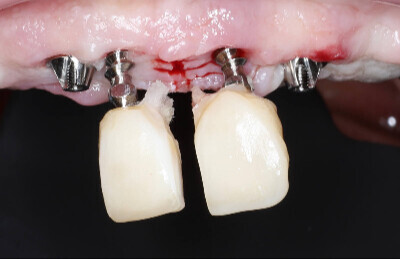

Navigovaná chirurgia, 5 implantátov

Autor práce Dr. Michal Repaši

Zubný technik Vasil Csopej

22. september 2021